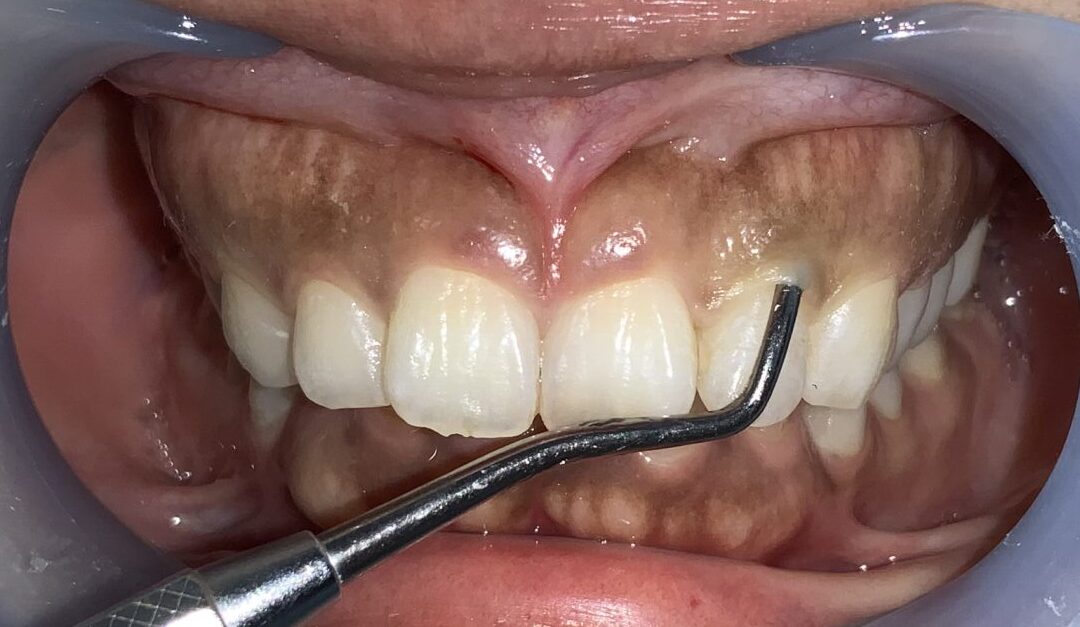

まずは1本だけ歯ぐきの整形を行なって、患者様に確認をして頂きます。

歯ぐきの面積が小さくなり、歯が大きくなり、歯ぐきの形が整っています。

片側だけ終わりました。患者様にも確認をして頂きます。歯ぐきの形、歯の形、笑った時の歯ぐきの見え方を全てご確認頂きました。

患者様にも仕上がりに納得して頂きました。